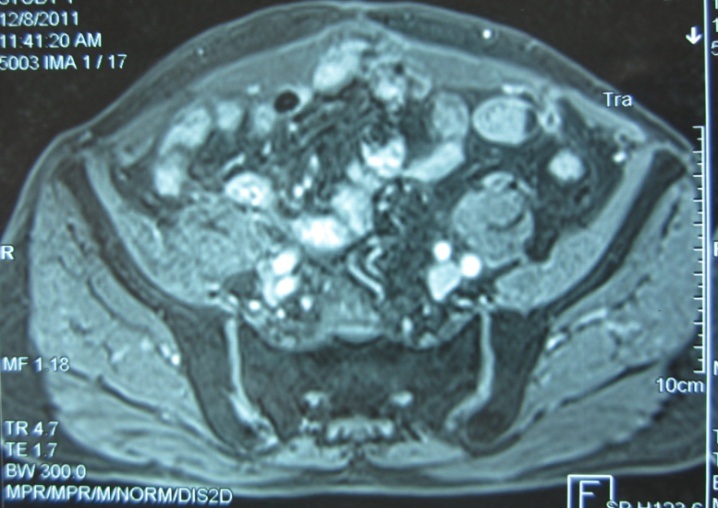

Kết quả sau liệu trình hóa - xạ trị: khối tổn thương tan hết trên hình ảnh cộng hưởng từ tiểu khung

Hình ảnh chụp MRI vùng tiểu khung: khối u tan hoàn toàn